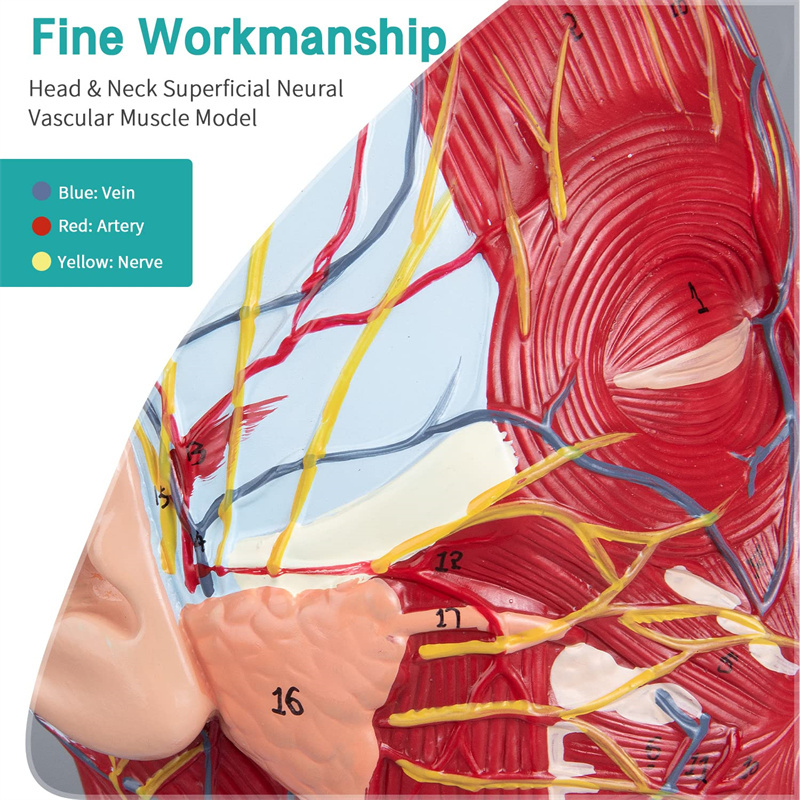

【Imodeli ye-Neurovascular yemisipha ekhethekile enemininingwane eminingi, izinombolo ezimakwe kakhulu, izindlebe ezivinjelwe, zijulisa ukuqonda kwemisipha engaphezulu, imikhumbi, izinzwa kanye nezinhlaka zangaphakathi zekhanda nentamo. I-Red-artery, i-Blue-Vein, i-Yellow-Nerve.

Izici 【Izici】 Kubonisa izicubu ezingezinhle zobuso obudaluliwe; Imithambo yegazi engekho emthethweni nezinzwa zobuso ne-scalp; Izakhiwo ezingaphakathi ze-Parotid Gland & Upper Respiratory Tract; isakhiwo sesigaba se-sagittal somgogodla wesibeletho.

Le modeli iyinhloko enkulu yemvelo nemodeli ye-neurovascular yemisipha eyindilinga, isakhi esingu-1, ekhombisa imininingwane yekhanda lelungelo lomuntu kanye nentamo kanye nengxenye ye-Median Sagittal, okubandakanya imisipha engemihle yobuso, imithambo ephakeme yobuso obukhulu bobuso kanye nesikhumba, izinzwa nokwakheka kwempilo kwe-parotid gland kanye nepheshana lokuphefumula elingaphezulu, kanye nesakhiwo seSigaba se-sagittal somgogodla wesibeletho